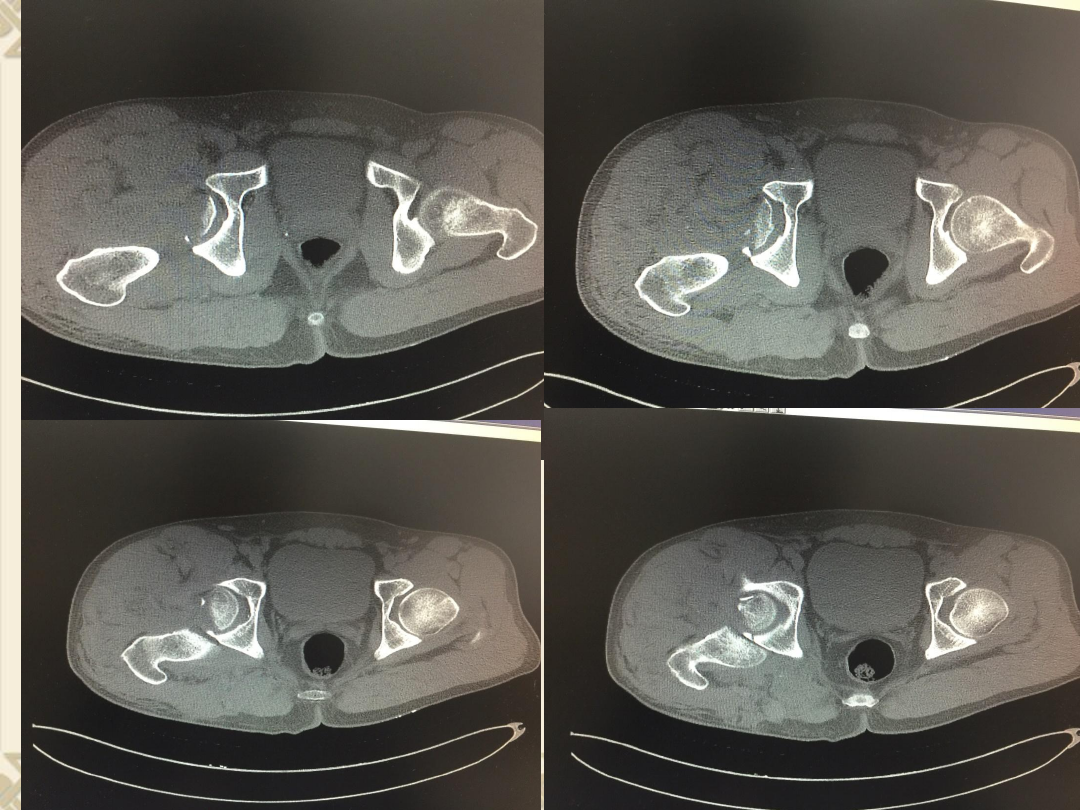

CT

v

、右股骨头骨折(

Pipkin

Ⅳ型骨折)

2

、髋关节后脱位

3

、髋臼后缘骨折